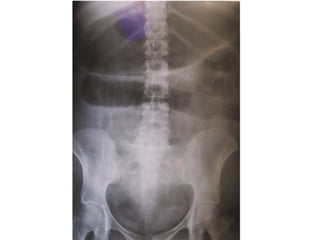

• RADIOLOGIA

• Teleradiografia de torax PA y lateral  Aire libre

subdiafragmatico

• Placas simples de abdomen

• De cúbito  Patrones gaseoso

• De pie o de cúbito lateral  Niveles hidroareos

• Estudio baritado con control de fluoroscopio

• TAC